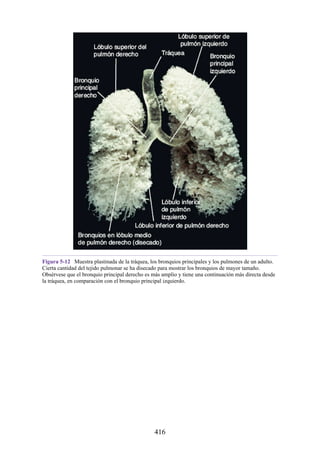

4. Anatomía radiológica. Cada capítulo incluye numerosas imágenes

médicas estándar (p. ej., radiografías, tomografías computarizadas,

resonancias magnéticas y ecografías) para mostrar la anatomía normal de

la manera en que los médicos suelen observarla. Las fotografías

etiquetadas de secciones transversales anatómicas estimulan a los

estudiantes a pensar en términos de anatomía tridimensional, que es

fundamental en la interpretación de los estudios de imagen.